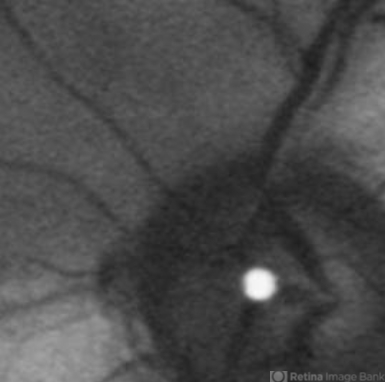

- Branch Retinal Artery Occlusion

- branch retinal artery occlusion (BRAO), embolus, retinal edema, fundus autofluorescence (FAF)

- Acute branch retinal artery occlusion with a calcium embolus at the disc which is hyper autofluorescent in fundus autofluorescence imaging (FAF) -resembles an LED light source ('LED sign').